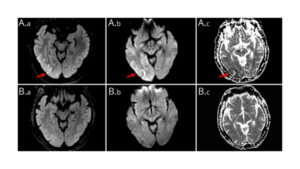

高血糖誘発性に発症する「後頭葉てんかん」についてneuroimageで報告されています。迅速な診断と血糖値の是正が必要になります。他科から相談された際に、鑑別に入れるべき疾患・画像所見ですね。

※詳細は以下の画像をクリックしてご覧ください。